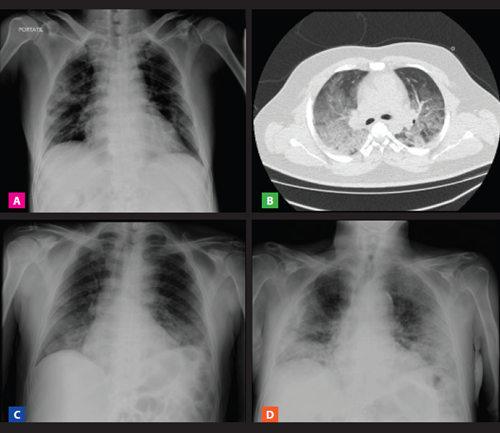

Se realizó radiografía de tórax en 9 pacientes y tomografía pulmonar en 2 casos, no habiéndose realizado estudios en los primeros casos por no disponer de equipos o disposiciones específicas para trasladar a los pacientes al área de radiodiagnóstico. Se encontraron alteraciones radiológicas bilaterales en todos los casos, predominando patrón intersticial en vidrio esmerilado (en 6 de los 9 casos) y patrón mixto alveolar e intersticial en los otros 3 casos (Figura 1).

Figura 1 Estudios radiológicos de pacientes fallecidos por COVID-19, en un hospital terciario de Lima, Perú (A) Varón 61 años con diabetes e hipertensión arterial, muestra patrón intersticial en vidrio esmerilado bilateral. (B) Varón 26 años antecedente de asma bronquial y obesidad, con predominio de lesiones intersticiales en vidrio esmerilado. (C) Varón 66 años sin antecedentes y con patrón alveolo-intersticial bilateral. (D) Mujer 97 años antecedente de hipertensión arterial, con lesiones alveolo-intersticiales bilaterales